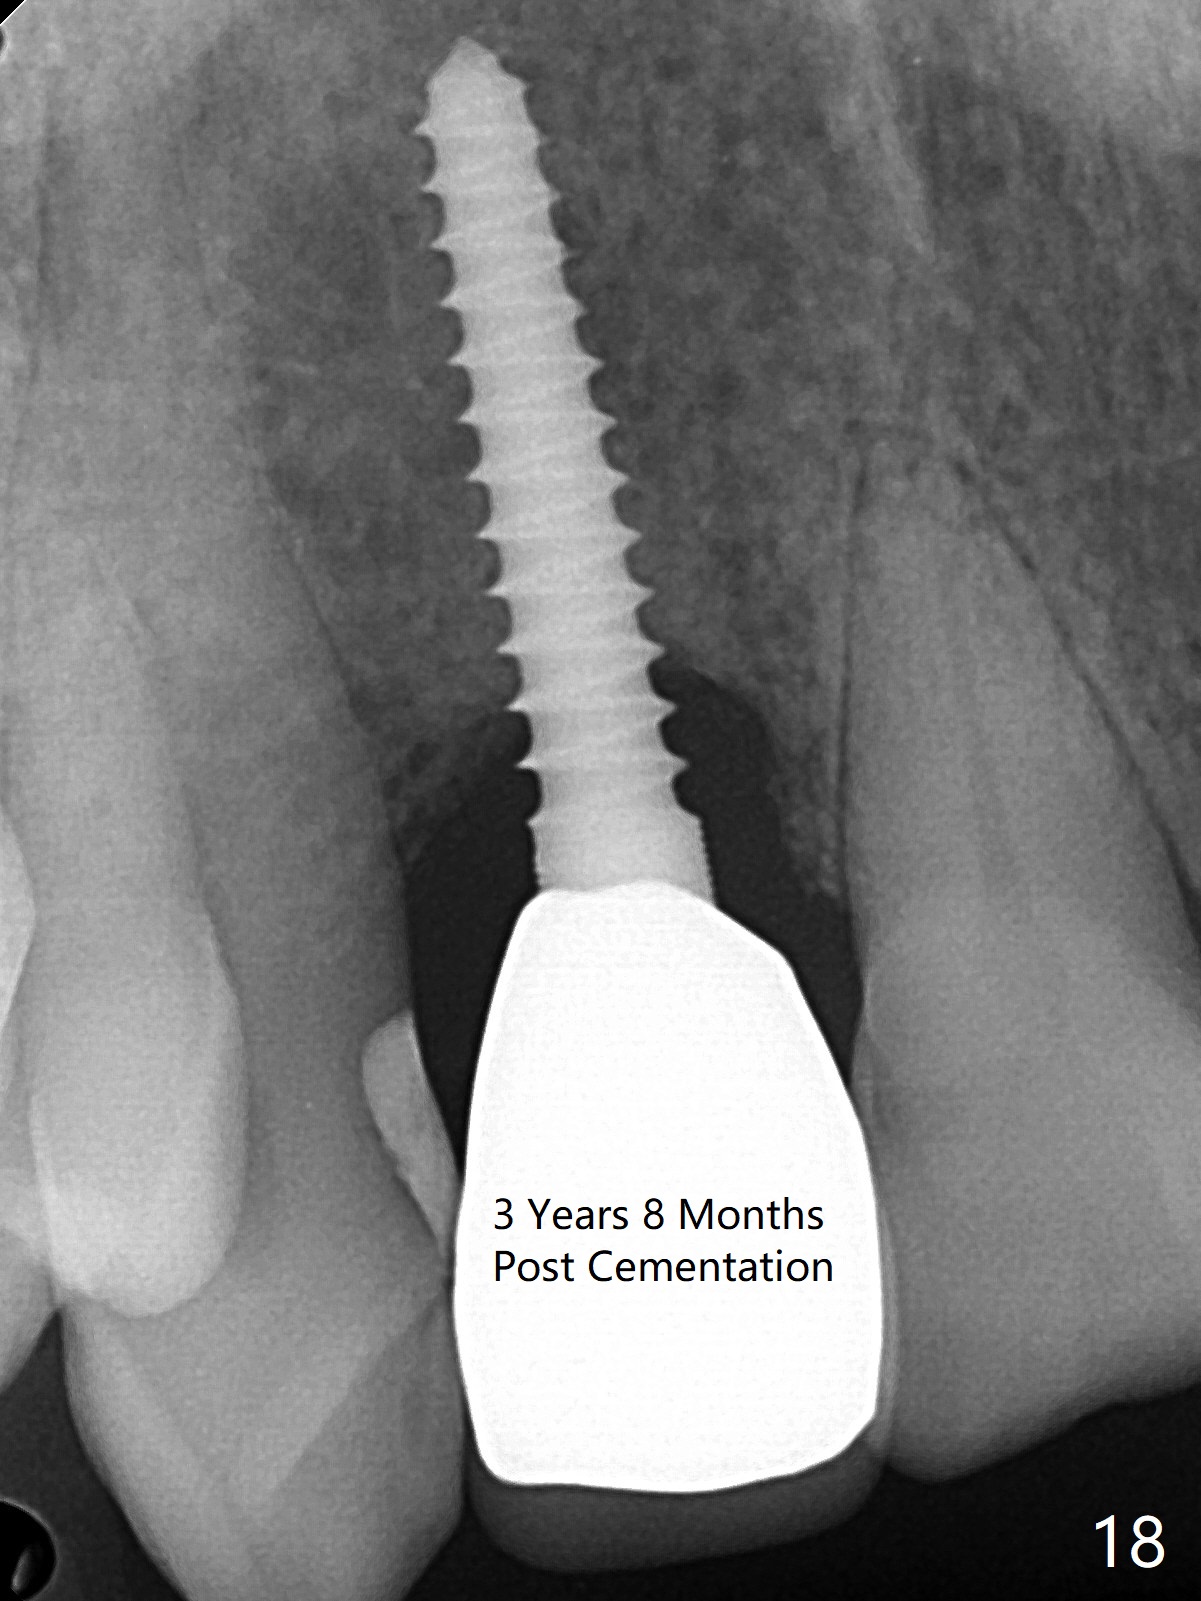

Sixteen days postop, the patient is doing fine, although the labial fistula has not disappeared (Fig.8 <). The detached distolabial papilla is healing (Fig.9 *) with mild bone graft exposure (^). The lacerated distopalatal papilla is also healing (Fig.10 *). These complications are related to flap surgery. The apical portion of the socket appears to have reduced 4 months postop (Fig.14). When the definitive restoration is delivered 5 months postop, there is gingival recession, including the distal of #8 (Fig.11 arrows, which is expected to improve over time) due to flap surgery. The labial plate collapse is minimal (Fig.12 *), while the palatal laceration (Fig.10) has healed (Fig.13). When the patient returns 1.5 years post cementation, there is increased bone density next to the coronal portion of the implant, equivalent to the bone graft (Fig.15 *). The fistula is absent (Fig.16). The crestal bone loss remains 2.5 years post cementation (Fig.17 *), although there is no sign of periimplantitis (magnification). Oral hygiene is poor. There is no change in the soft (gingival recession; data not shown) or hard tissues 3 years 8 months post cementation (Fig.18).